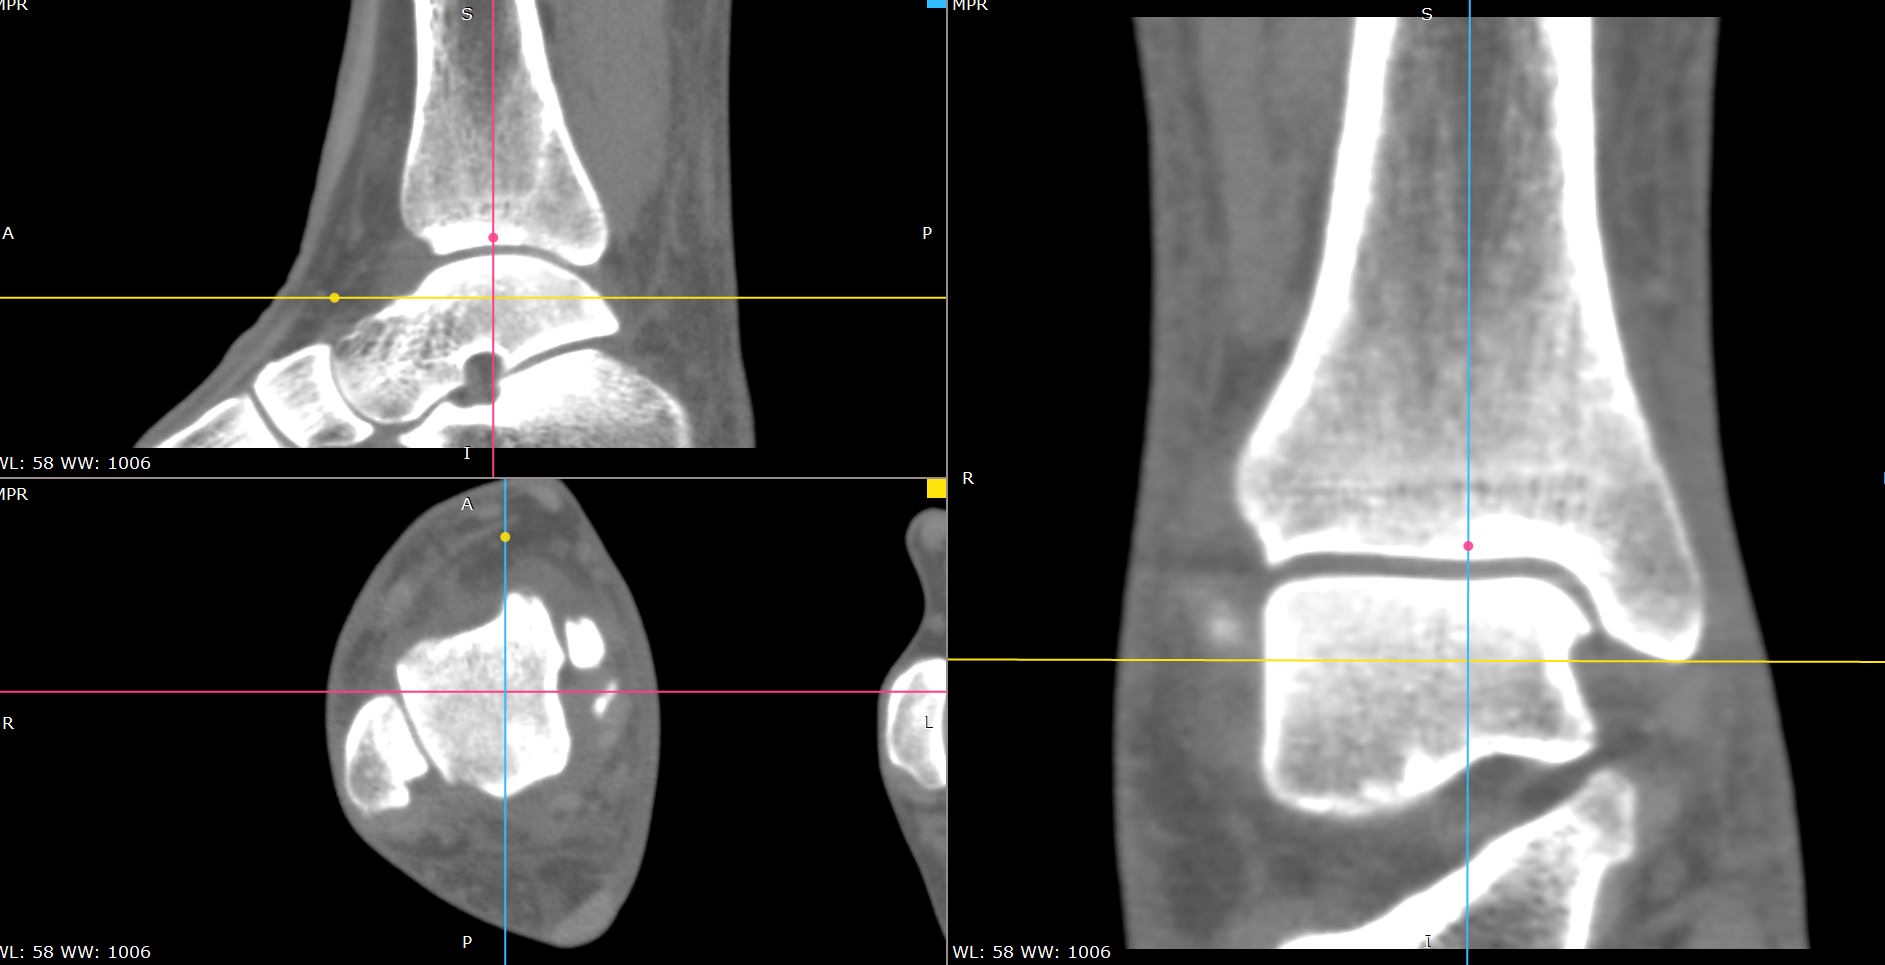

Мультиспиральная компьютерная томография является современным лучевым методом исследования, который позволяет с помощью рентгеновского излучения получить посрезовые снимки и после цифровой обработки создать объемные модели исследуемой области в мельчайших подробностях. Рентгеновские лучи в большей степени поглощаются плотными тканями организма, поэтому на снимках хорошо визуализируются кости скелета. Для более детальной оценки состояния мягкотканных структур зачастую проводится контрастное усиление.

В наших медицинских центрах КТ мягких тканей конечностей выполняется на современных мультиспиральных компьютерных томографах экспертного уровня TOSHIBA AQUILION. Аппараты послойно сканируют область исследования, одномоментно выполняя множество тончайших срезов. В результате получаются снимки высокого качества и трехмерные модели с изображением костного скелета и мягких тканей конечностей. При этом методика скоростного мультисрезового сканирования обеспечивает минимальную дозу рентгеновского облучения для пациента.